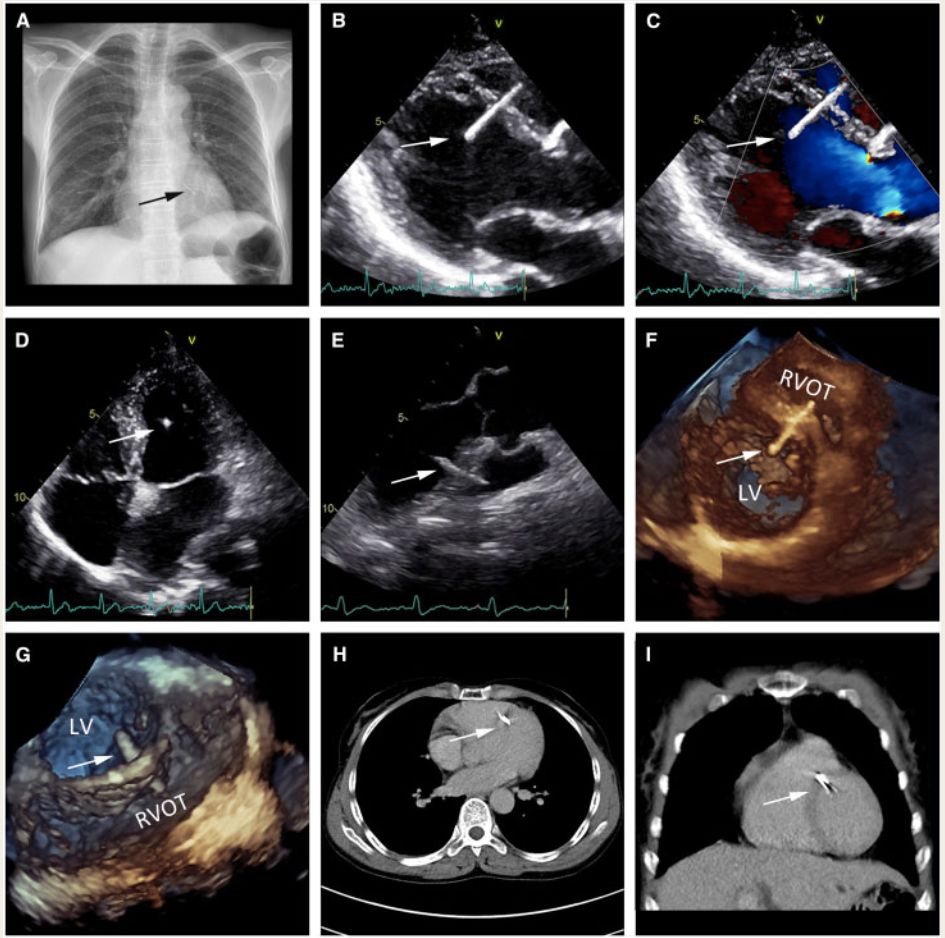

一个不寻常的病例:心脏上的绣花针